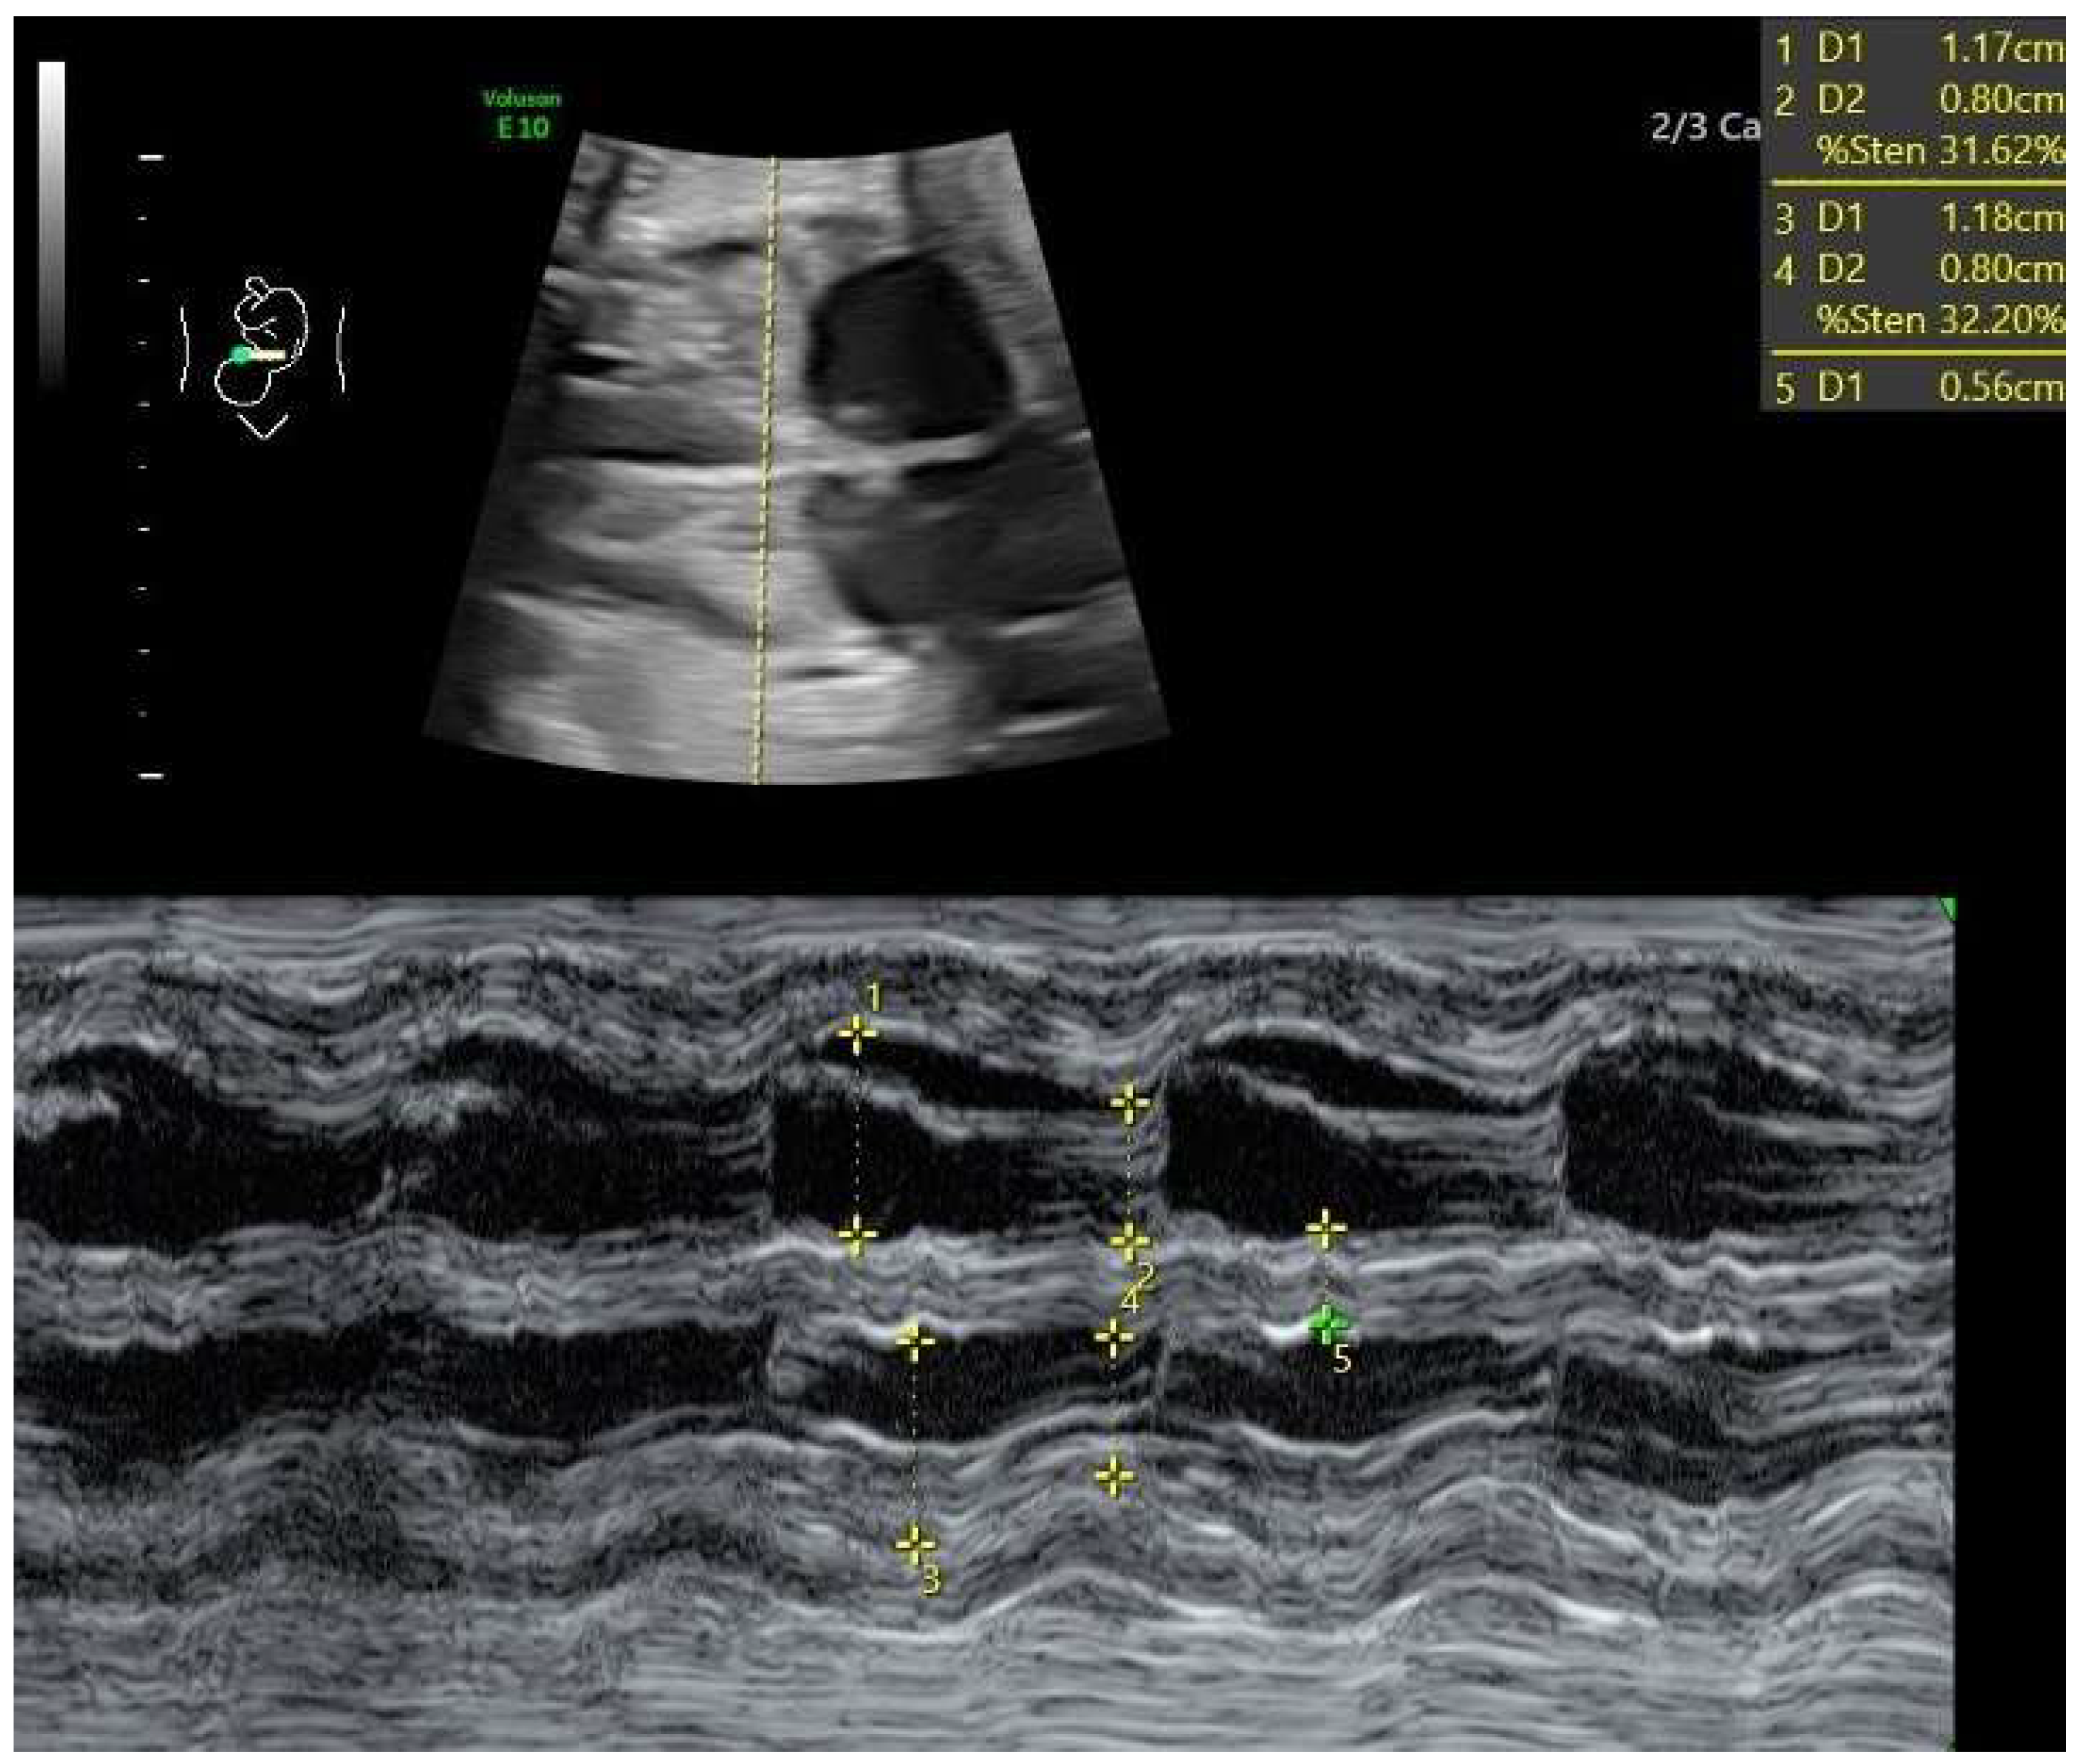

- Ductal constriction (DC), defined as a peak systolic velocity (PSV) > 1.4 m/s or >95th percentile for gestational age, a peak diastolic velocity > 35 cm/s or >95th percentile, or a pulsatility index (PI) < 1.9 [8,9]. The measurement was taken by visualizing the DA at the 12th or 6th “hour” (+/− 30 degrees), which was performed by seeing the ductal arch in the long-axis view. Fetal slow movements or hiccups were accounted for and if they occurred the measurement was taken more times during the examination (Figure 2).

- Szmyd, B.; Biedrzycka, M.; Karuga, F.F.; Rogut, M.; Strzelecka, I.; Respondek-Liberska, M. Interventricular Septal Thickness as a Diagnostic Marker of Fetal Macrosomia. J. Clin. Med. 2021, 10, 949. [Google Scholar] [CrossRef]